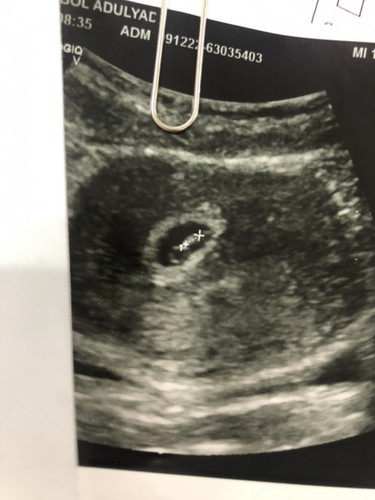

แม่บ้านนี้เมื่อคืนปวดท้อง ถี่แล้วท้องแข็ง ตอนเช้าเลยตื่นไปหาหมอค่ะ หมอบอกปากมดลูกเปิด1เซน แต่อายุครรภ์แค่27สัปดากับ4วัน เค้รจะให้นอนรพ เพื่อนฉีดยากระตุ้นปอดกับยาระยับคลอด แต่แม่ไม่อยากฉีกค่ะเคยฉีดแล้วคนล่าสุดก้คลอดก่อนกำหนดค่ะ แต่แม่ก้ดีขึ้นไม่ได้ปวดถี่ขึ้นแล้วอาการปวดก้ลดลง น้องดิ้นปกติดิ้นแรงด้วยค่ะ #ขอคำแนะนำกับแม่ๆด้วยนะคะ